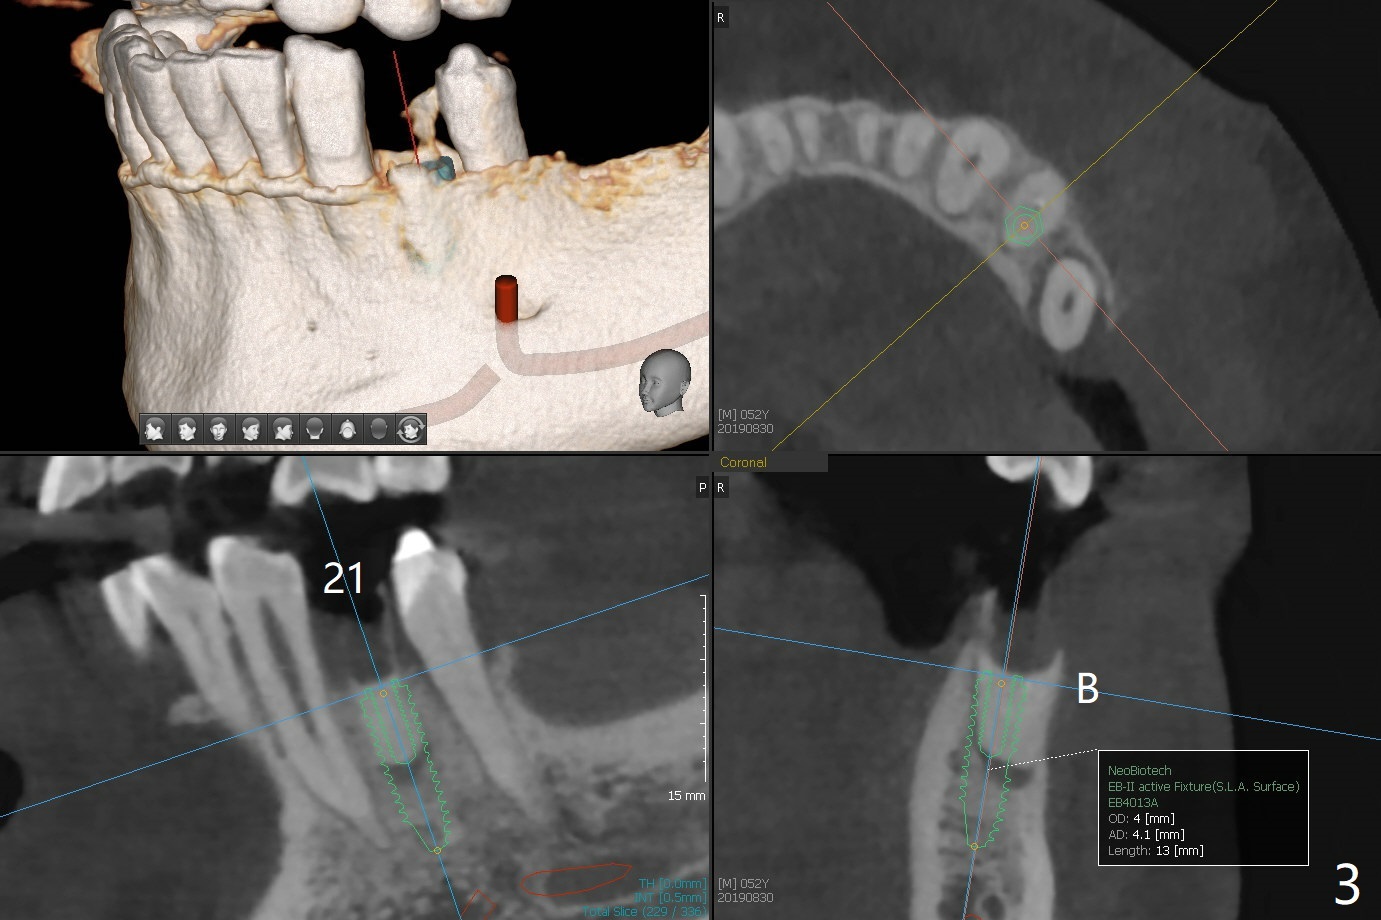

A 52-year-old man chooses to take care of the teeth #21 and 29 first due to finance (Fig.1). The implant diameter should not be too large because of the moderate mesiodistal space (Fig.2,3). Since the buccal plate of #21 is indistinct (socket shield will be done), the implant should be a little more lingually placed than the design in Fig.3, although the implant placement level seems to be acceptable. Socket shield seems to be necessary.